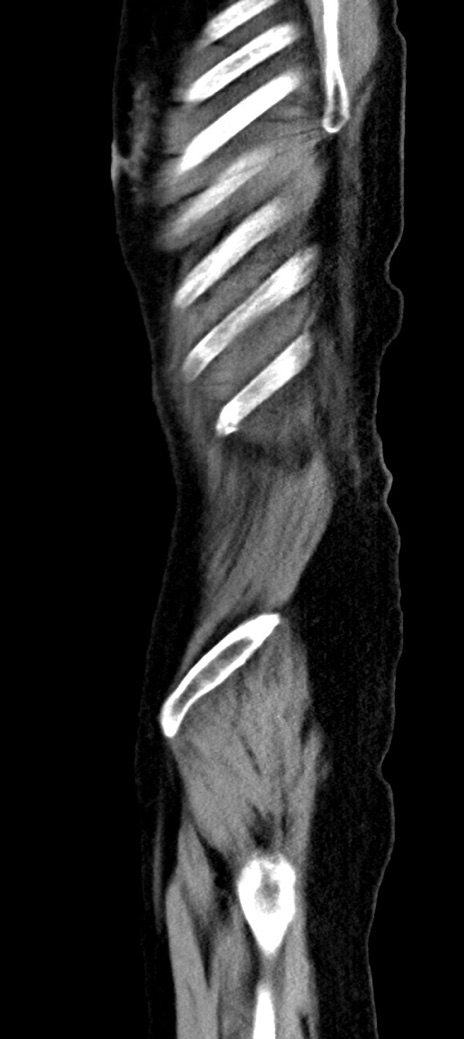

他院CT

横断像

冠状断像